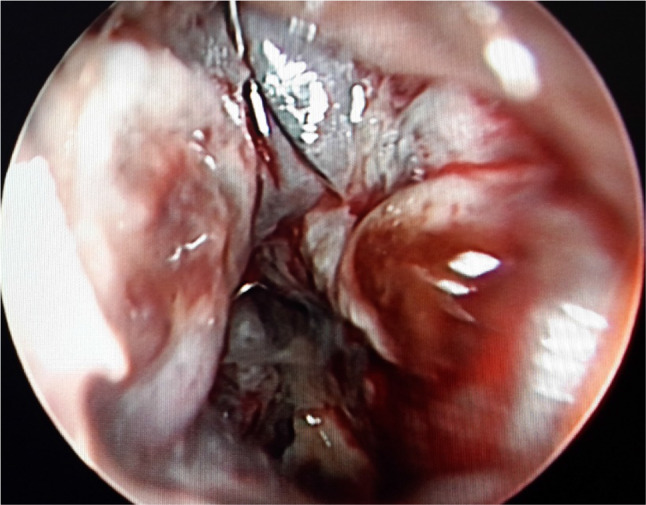

Preliminary blood investigations were found to be normal. Diagnostic nasal endoscopy revealed a greyish friable mass with irregular surface on left nasal cavity,bleeding on touch involving the whole of the left middle meatus, posteriorly extending up to choana and displacing the septum to the opposite side (Figs. 3, 4). At the same sitting, a biopsy of the lesion was taken and sent for histopathological examination.

Fig. 3.

DNE: Greyish mass filling whole of left middle meatus and extending till choana posteriorly